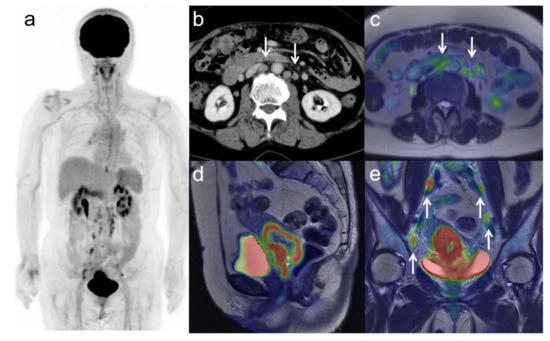

Figure 1. A 54-year-old woman with stage IIIC1 cervical cancer with parametrial invasion. (a) 18F-FDG PET image shows FDG uptake by tumor in the cervical cervix (arrow) and pelvic lymph nodes. (b) Axial T2-weighted pelvic MR image shows parametrial invasion with disruption of the right cervical stroma by the tumor but no extension into the pelvic side wall (arrow). (c) Axial T2-weighted PET/MR image shows FDG uptake by the tumor, which invades the right parametrium with disruption of the cervical stroma, but no extension into the pelvic side wall (arrow). These appearances are consistent with the clinical findings. (d) Sagittal T2-weighted PET/MR image shows FDG uptake by the cervical tumor. (e) Coronal T2-weighted PET/MR image shows FDG uptake by the cervical tumor and pelvic lymph nodes (arrows).

3.3. Revised FIGO Staging